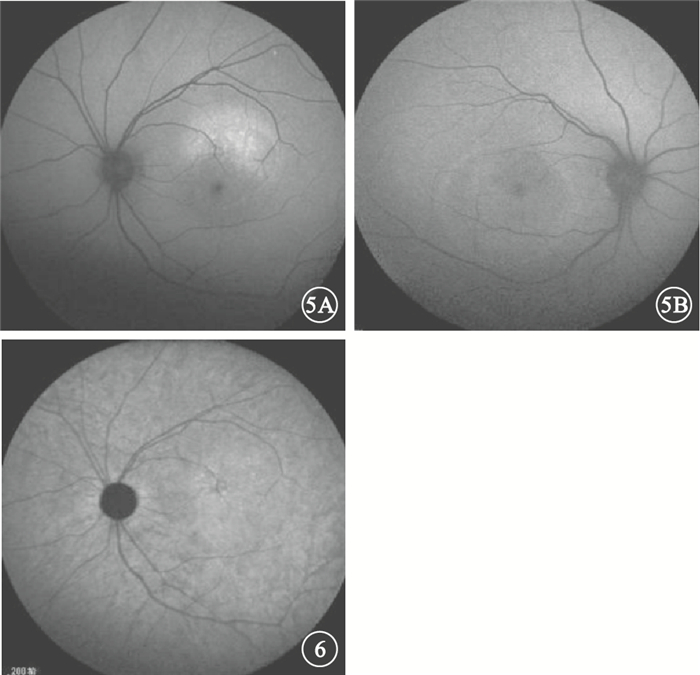

慢性CSC 34只眼中,與FFA檢查可見的滲漏點對應處BLAF表現以點狀或片狀強熒光(圖 5A)為主,其次是無異常改變者,表現為點狀、片狀弱熒光(圖 5B)或斑駁熒光者較少。可觀察到神經上皮層脫離(圖 5B)14只眼,占41.2%。其中,表現為圓形或橢圓形弱熒光9只眼,占65.3%;表現為強熒光5只眼,占35.7%。IRAF表現以點狀、片狀弱熒光或斑駁熒光(圖 6)為主,其次為點狀或片狀強熒光,較少數無明顯改變。可觀察到神經上皮層脫離僅3只眼,占8.8%;均表現為類圓形弱熒光(表 2)。

慢性CSC患眼BLAF像。5A.圖 2A同眼,與FFA檢查可見的滲漏點對應處表現為點狀強熒光;5B.圖 2B,與FFA檢查可見的滲漏點對應處表現為片狀弱熒光,周圍可見類圓形神經上皮層脫離??圖 6?圖 2A同眼IRAF像。與FFA檢查可見的滲漏點對應處表現為斑駁熒光

圖5

慢性CSC患眼BLAF像。5A.圖 2A同眼,與FFA檢查可見的滲漏點對應處表現為點狀強熒光;5B.圖 2B,與FFA檢查可見的滲漏點對應處表現為片狀弱熒光,周圍可見類圓形神經上皮層脫離??圖 6?圖 2A同眼IRAF像。與FFA檢查可見的滲漏點對應處表現為斑駁熒光

慢性CSC 34只眼中,與FFA檢查可見的滲漏點對應處BLAF表現以點狀或片狀強熒光(圖 5A)為主,其次是無異常改變者,表現為點狀、片狀弱熒光(圖 5B)或斑駁熒光者較少。可觀察到神經上皮層脫離(圖 5B)14只眼,占41.2%。其中,表現為圓形或橢圓形弱熒光9只眼,占65.3%;表現為強熒光5只眼,占35.7%。IRAF表現以點狀、片狀弱熒光或斑駁熒光(圖 6)為主,其次為點狀或片狀強熒光,較少數無明顯改變。可觀察到神經上皮層脫離僅3只眼,占8.8%;均表現為類圓形弱熒光(表 2)。

慢性CSC患眼BLAF像。5A.圖 2A同眼,與FFA檢查可見的滲漏點對應處表現為點狀強熒光;5B.圖 2B,與FFA檢查可見的滲漏點對應處表現為片狀弱熒光,周圍可見類圓形神經上皮層脫離??圖 6?圖 2A同眼IRAF像。與FFA檢查可見的滲漏點對應處表現為斑駁熒光

圖5

慢性CSC患眼BLAF像。5A.圖 2A同眼,與FFA檢查可見的滲漏點對應處表現為點狀強熒光;5B.圖 2B,與FFA檢查可見的滲漏點對應處表現為片狀弱熒光,周圍可見類圓形神經上皮層脫離??圖 6?圖 2A同眼IRAF像。與FFA檢查可見的滲漏點對應處表現為斑駁熒光